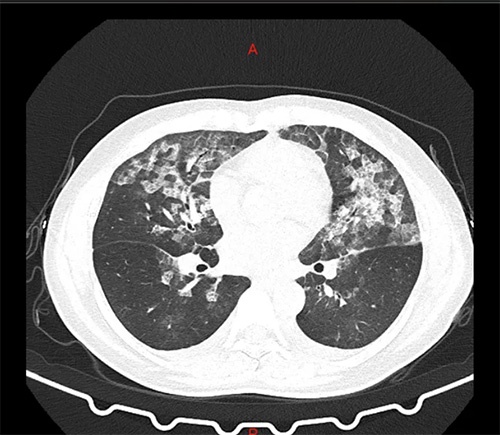

两女子滥用84消毒液:长期吸入致肺部ct影像与新冠肺炎